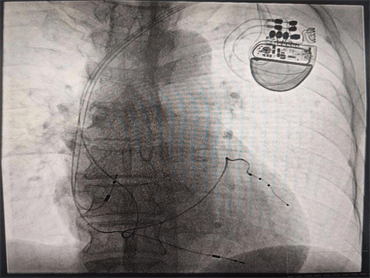

8月9日晚,心血管內(nèi)科九病區(qū)崔旭輝主任團(tuán)隊成功開展了CRT-P(簡稱三腔起搏心臟再同步化起搏器)。該手術(shù)成功實施,為此類患者的治療提供了一個新的保障,也標(biāo)志著我科心力衰竭介入治療技術(shù)又上了一個新臺階,具有重大意義。

由于患者心功能差,身材消瘦,且情緒較為焦慮,術(shù)后易伴并發(fā)癥,心血管內(nèi)科九病區(qū)醫(yī)療團(tuán)隊針對該患者的情況進(jìn)行術(shù)前討論研究,護(hù)理團(tuán)隊采用敘事護(hù)理的方法解除了患者的焦慮情緒,在充分考量患者的個體因素后,經(jīng)患者及家人同意,確定手術(shù)方案。術(shù)中,崔主任親切的語言緩解了張大爺?shù)慕箲],在平靜的狀態(tài)下成功將三個電極植入到右心房、右心室、左心室(冠狀靜脈分支遠(yuǎn)端)圓滿完成了手術(shù)。術(shù)后,反復(fù)程控參數(shù),達(dá)到起搏器工作狀態(tài)最優(yōu)化,復(fù)查心電圖示QRS波恢復(fù)到107ms,明顯變窄,患者心臟功能及癥狀較手術(shù)前顯著改善,遠(yuǎn)期療效在進(jìn)一步觀察中,將通過不斷程控,優(yōu)化心臟起搏器參數(shù),達(dá)到更好的治療效果,崔主任親自為患者按時換藥,術(shù)后切口愈合良好。通過護(hù)士長魏薇及護(hù)理團(tuán)隊的精心指導(dǎo),張大爺術(shù)后的康復(fù)鍛煉也非常順利。

心臟再同步化治療(CRT或者CRT-P)是近年來發(fā)展迅速的治療心力衰竭患者的重要手段,它是將電極植入右心房、右心室及左心室三腔起搏,使左右心室同步激動,同步收縮,改善心臟功能,降低心力衰竭患者病死率,是心力衰竭者的新希望,是心力衰竭治療史上一個里程碑的突破。